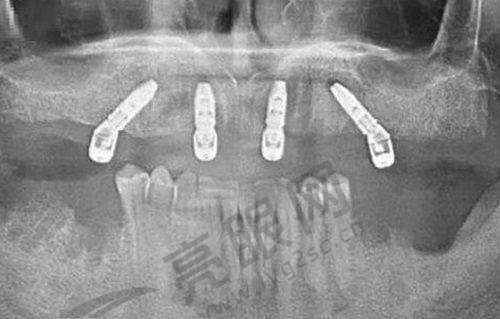

有一位25岁的女性地包天患者,经18个月隐形矫正后,颌面比例变得协调,从以前的“不敢笑”变成了现在的“自信露齿”。还有一位38岁的男性龅牙伴牙槽骨萎缩患者,采用种植 + 正畸联合治疗,半年就修复了咀嚼功能,生活质量得到了极大的提升。